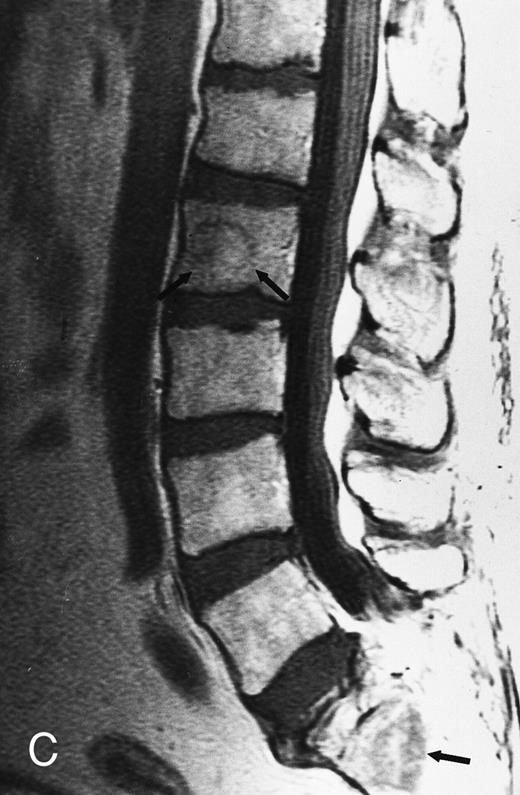

Diffuse MR pattern of abnormal marrow in a 29-year-old man with AML: T1-weighted sagittal (500/10, TR/TE) (A), T2-weighted, fat-suppressed fast spin echo sagittal (5000/96, TR/TE, ET 16) (B), and enhanced T1-weighted sagittal (500/10, TR/TE) (C) MR images of the thoracic spine. The abnormal vertebral bodies in (A) are dark and isointense to the intervertebral discs and in (B) they become bright. In (C), the abnormal marrow enhances and the vertebrae become brighter than the discs. Note extraosseous mass (arrowheads) in the posterior epidural space with preservation of the bony cortex.